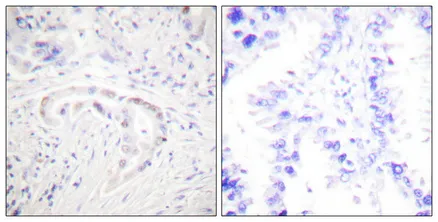

PKC ζ (phospho Thr410) Rabbit Polyclonal Antibody

Cat: APRab05264

Size1:50μl Price1:$128

Size2:100μl Price2:$230

Size3:500μl Price3:$980

Size2:100μl Price2:$230

Size3:500μl Price3:$980